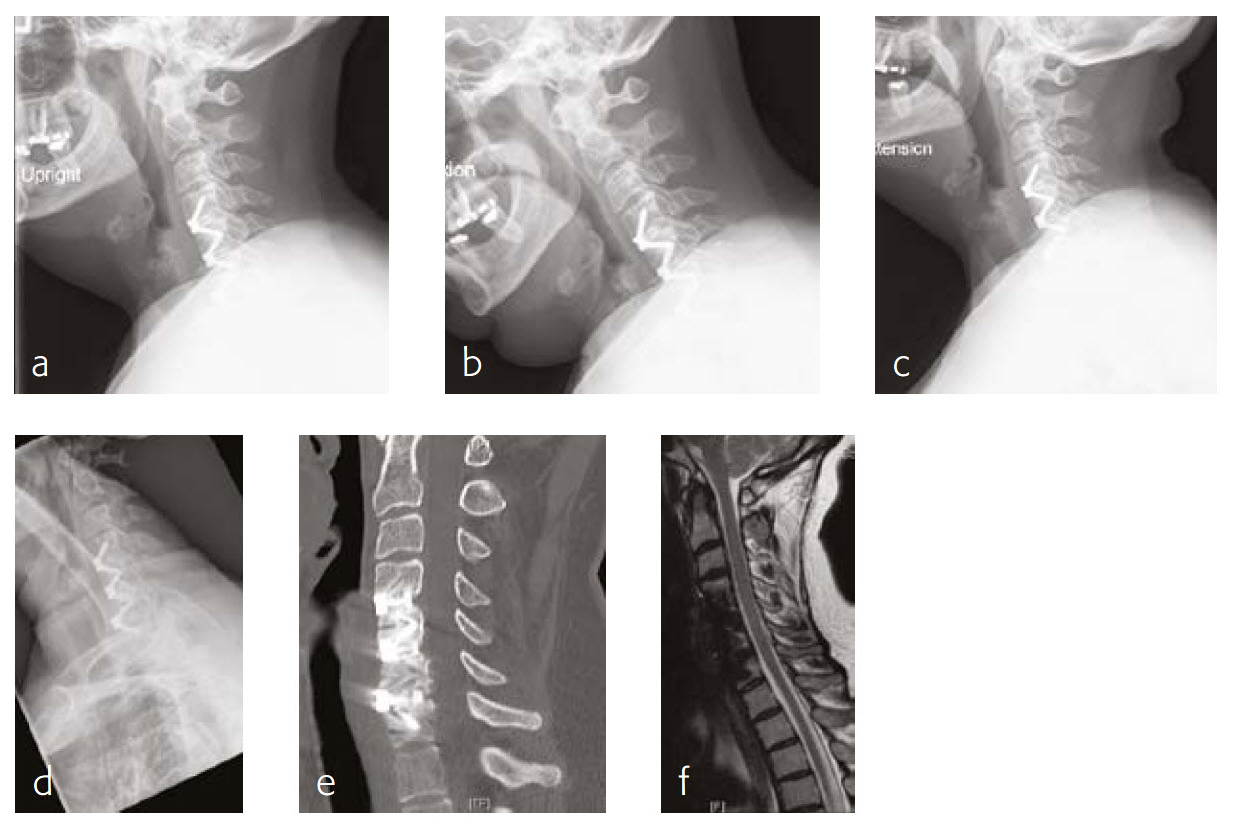

Case 3: A 46-year-old woman with neck pain and upper extremity paresthesia

A 46-year-old woman presented with one-year history of neck pain, upper extremity paresthesia, weakness, and subjective numbness (Fig 5). Her right upper extremity was worse than her left, with loss of function and debilitating pain. She described cramping in her upper extremities without etiology and without alleviating factors.

She had not been responsive to anti-inflammatory medications nor other nonoperative treatment including physical therapy. She had trouble with many of her activities of daily living due to breaks that must be taken due to her pain, as well as the inability to do certain things like open jars due to weakness.

Musculoskeletally, she had no obvious deformity in any of her extremities. Her bilateral upper extremities had strength testing of 5/5 in shoulder abduction, elbow flexion/extension, wrist extension/flexion, and finger abduction/flexion. Bilateral lower extremities showed 5/5 strength with hip flexion bilaterally, as well as bilateral 5/5 strength knee extension, dorsiflexion, plantar flexion of the ankle, and firing EHL.

She had sensation that is intact in all dermatomes. She had no pathological reflexes and no clonus. There was normal tandem gait.

Review of the patients outside imaging showed congenital stenosis of the cervical spine, as well as multilevel disk disease and concomitant acquired stenosis in the foramen of C4-C5, C5-C6, and C6-C7 where it was at its most significant level.

Follow-up (4 months)

At the 4-month follow-up, the patients symptoms were largely resolved and she has been able to return to work (Fig 6). She was very satisfied with her outcome. made significant progress in terms of his left upper extremity range-of-motion and strength.